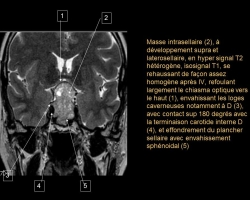

Un homme de 55 ans, n’ayant aucun antécédent personnel est envoyé pour réaliser une IRM par son ORL pour exploration d’acouphènes associés à une hypoacousie droite ainsi que des vertiges et une paralysie faciale périphérique droite d’apparition récente. […]